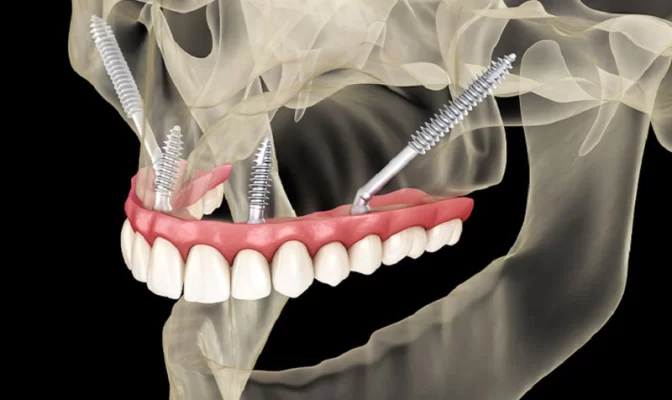

Zygoma Implants hay cấy ghép Implant xương gò má là phương pháp phục hình răng cho bệnh nhân mất răng hàm trên, bị tiêu xương nặng, không thể cấy ghép Implant như thông thường.

Khác biệt lớn nhất của Zygoma Implants là thay vì cấy vào xương hàm thì trụ Implant sẽ được cấy vào xương gò má. Như vậy, trụ Implant sẽ có lộ trình dài hơn, hình dáng thon dài và gấp khúc theo góc độ của vị trí răng mất. Tùy vào từng trường hợp mà bác sĩ sẽ chỉ định cấy 2 hoặc 4 trụ để hỗ trợ cầu răng toàn phần hoặc bán phần.

Đối với phương pháp này, xương gò má đóng vai trò như một cấu trúc nâng đỡ cho răng. Đây được xem là “ánh sáng cuối đường hầm” cho những bệnh nhân mất răng và không đủ điều kiện trồng răng Implant thông thường.

Số lượng trụ Implant tối ưu

Trụ Implant cấy từ xương gò má, được neo chặn ổn định và chắc chắn. Giúp nâng đỡ cấu trúc răng tối ưu mà không cần phải dùng quá nhiều trụ. Ngoài ra còn hạn chế các biến chứng không mong muốn khác như: đào thải trụ Implant, viêm quanh Implant, Implant rơi vào lòng xoang,…